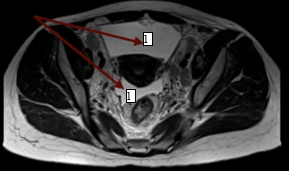

В дальнейшем была проведена МРТ органов малого таза с внутривенным контрастированием (рис. 3а, 3б). Было выявлено большое количество свободной жидкости, по задней поверхности брюшины и в пузырно-маточном углублении справа 2 узловых образования (канцероматоз), увеличенные лимфатические узлы во всех группах. Метастатические поражения костей таза.

Рис. 3б. Магнитно-резонансная томограмма органов малого таза с внутривенным контрастированием пациентки с раком желудка: скопление свободной жидкости в малом тазу (1)